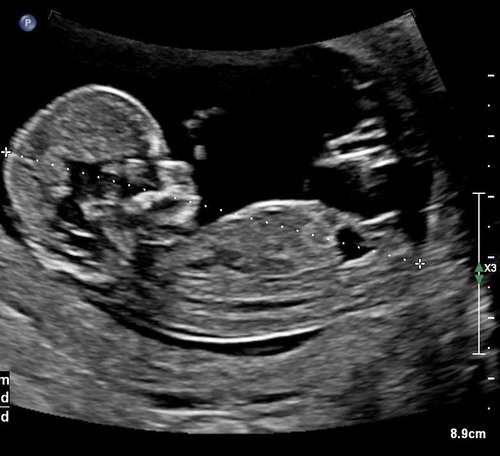

Wat denken jullie? 14 weken

Moet dit een potty shot zijn? Het is in elk geval geen nub foto, zou hem even in het potty shot topic plaatsen

Geen perfect pottyshot, maar ik denk 💙 zo was het bij ons destijds ook